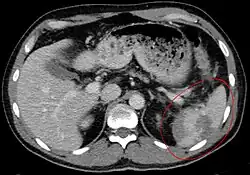

Splenic rupture is usually evaluated by FAST ultrasound of the abdomen.[5] Generally this is not specific to splenic injury; however, it is useful to determine the presence of free floating blood in the peritoneum.[5] A diagnostic peritoneal lavage, while not ideal, may be used to evaluate the presence of internal bleeding a person who is hemodynamically unstable.[6] The FAST exam typically serves to evaluate the need to perform a CT scan.[6] Computed tomography with IV contrast is the preferred imaging study as it can provide high quality images of the full peritoneal cavity.[5]